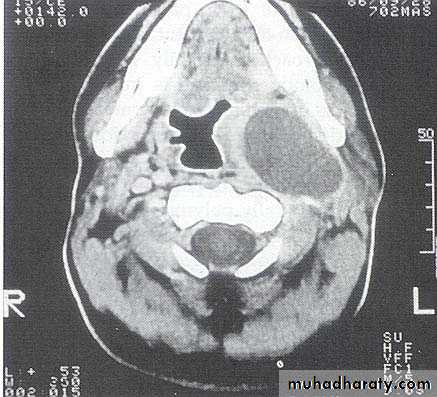

investigations

Complications:

• Acute oedema of the larynx• Thrombophlibitis of the int. jug. V.

• Spread to mediastinum.